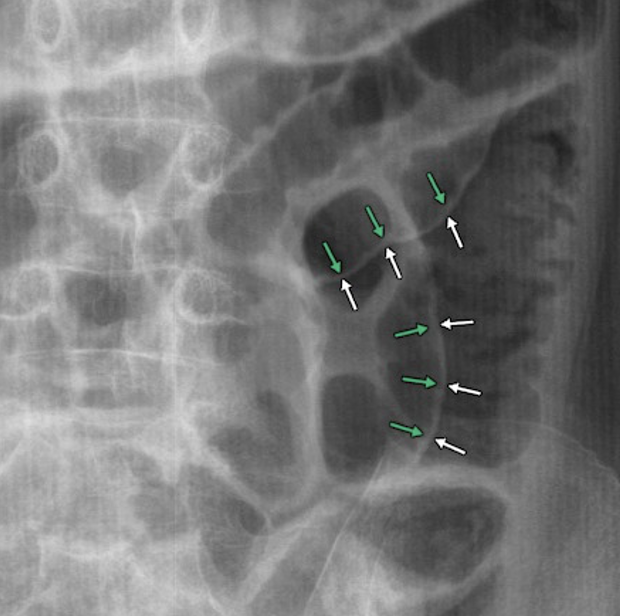

Answer: D) Sigmoid volvulus

Explanation: A coffee bean sign is shown which is an indication of a sigmoid volvulus, which is a condition where the sigmoid colon twists on its mesentery, causing obstruction.

A) is incorrect because thumbprinting is associated with colitis.

B) is incorrect because pneumoperitoneum is associated with Rigler’s sign characterised by the presence of air in the bowel wall (double wall sign).

C) is incorrect because caecal volvulus presents with the kidney bean sign.

E) is incorrect because small bowel obstruction shows dilatation of more than 3 cm and is characterised by the presence of plicae circularis/valvulae conniventes.